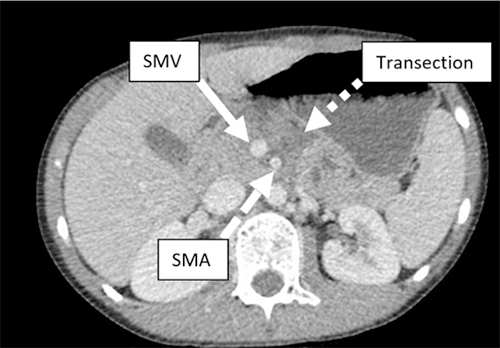

After crashing his bike and the handlebars striking his upper abdomen, a nine-year-old male patient presented with a pancreatic neck transection to our emergency department. He was hemodynamically stable with a normal exam aside from a circular bruise over the epigastrium with tenderness to palpation but no distension. A computed tomography (CT) abdomen and pelvis was obtained and showed a pancreatic laceration measuring 1.1 cm immediately anterior to the superior mesenteric vein (SMV) (Figure 1).

Figure 1. Axial Computed Tomography Scan of Patient's Abdomen. Published With Permission

Transection (dotted arrow) can be viewed close to portal vein (solid arrow) and superior mesenteric artery (dashed arrow).